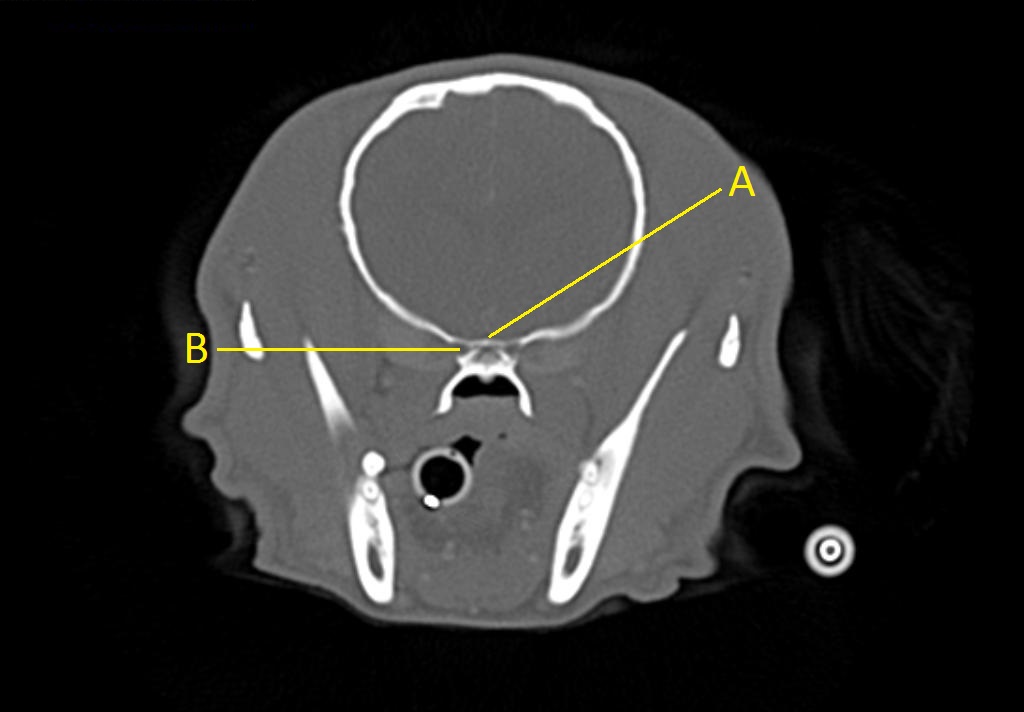

Q. Identify the structures labeled below:

A.

A. optic chiasm

B. orbital fissure